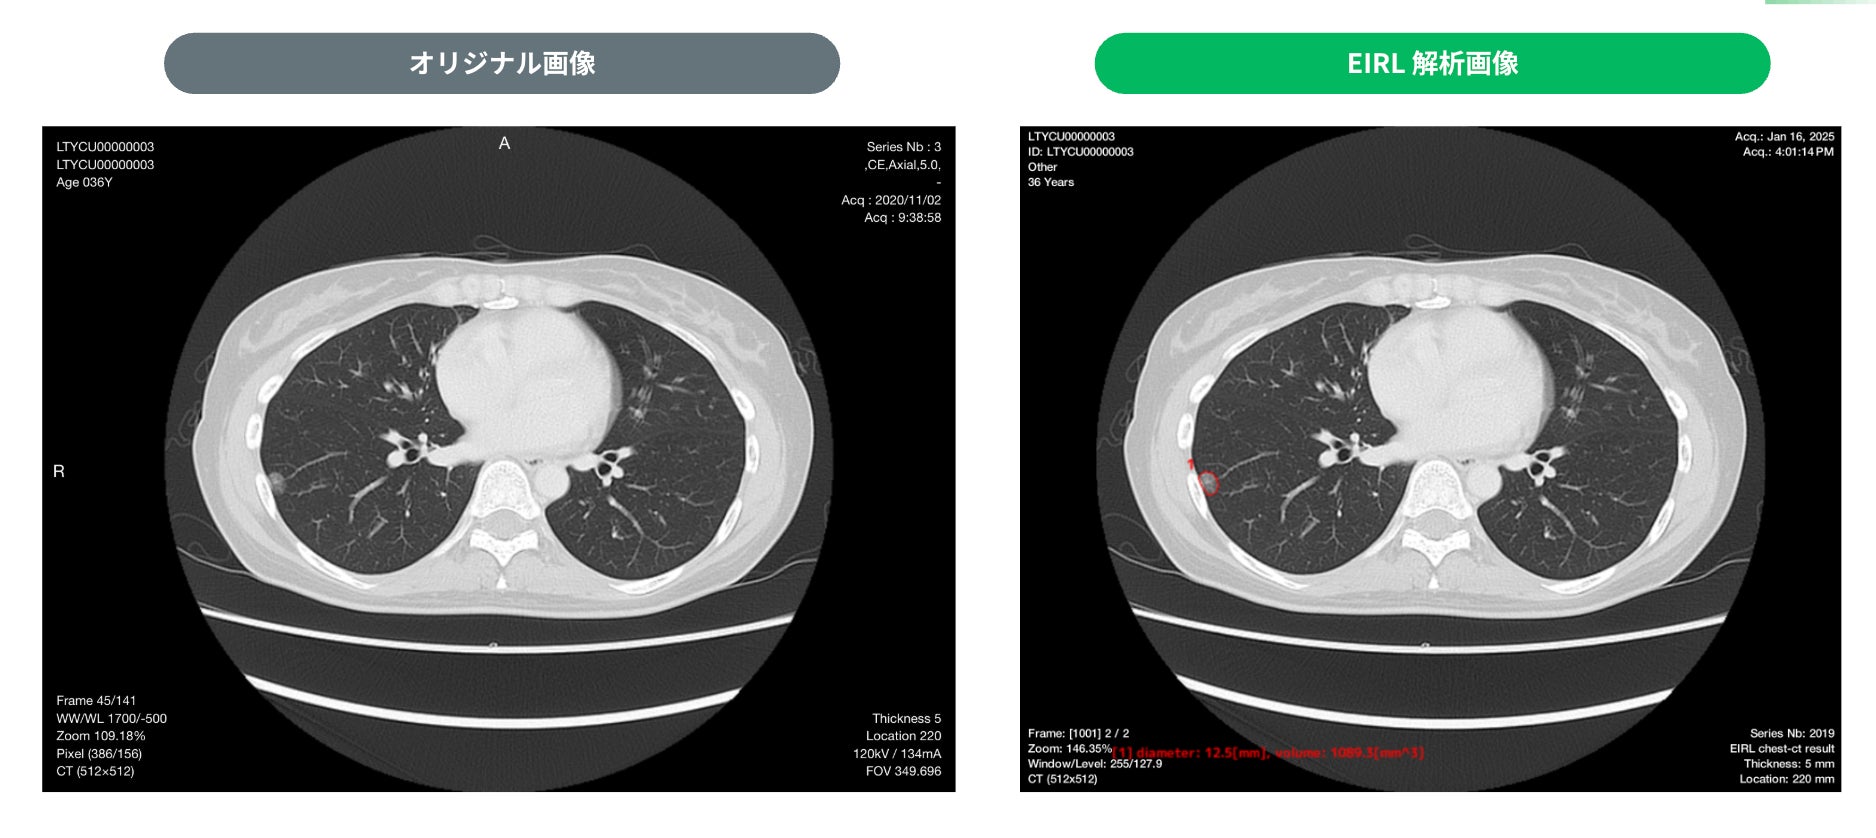

・検出例

③ 12.5mm すりガラス型